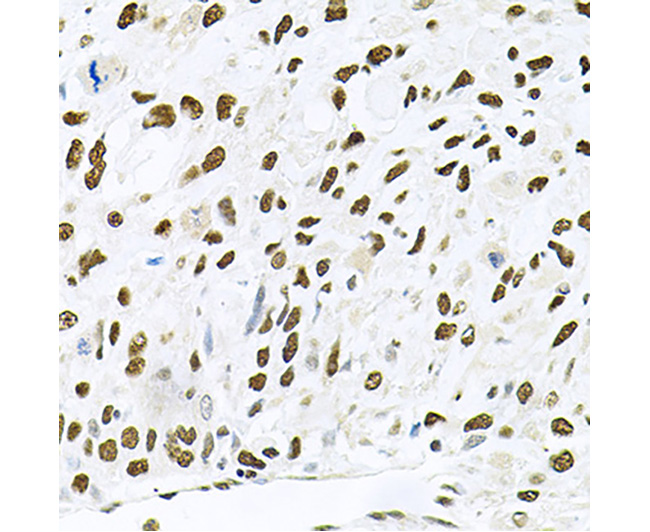

| Fig. 1. Western blot analysis of extracts of various cell lines, using JNK1 antibody at 1:1000 dilution. Secondary antibody: HRP-labeled Goat Anti-Rabbit IgG(H+L) (A0208) at 1:1000 dilution. Lysates/proteins: 25µg per lane. Blocking buffer: QuickBlock™ Blocking Buffer (P0231). Detection: BeyoECL Star (P0018A). Exposure time:1s. | Fig. 2. Immunohistochemistry of paraffin-embedded human lung cancer using JNK1 antibody at dilution of 1:100 (40x lens). |